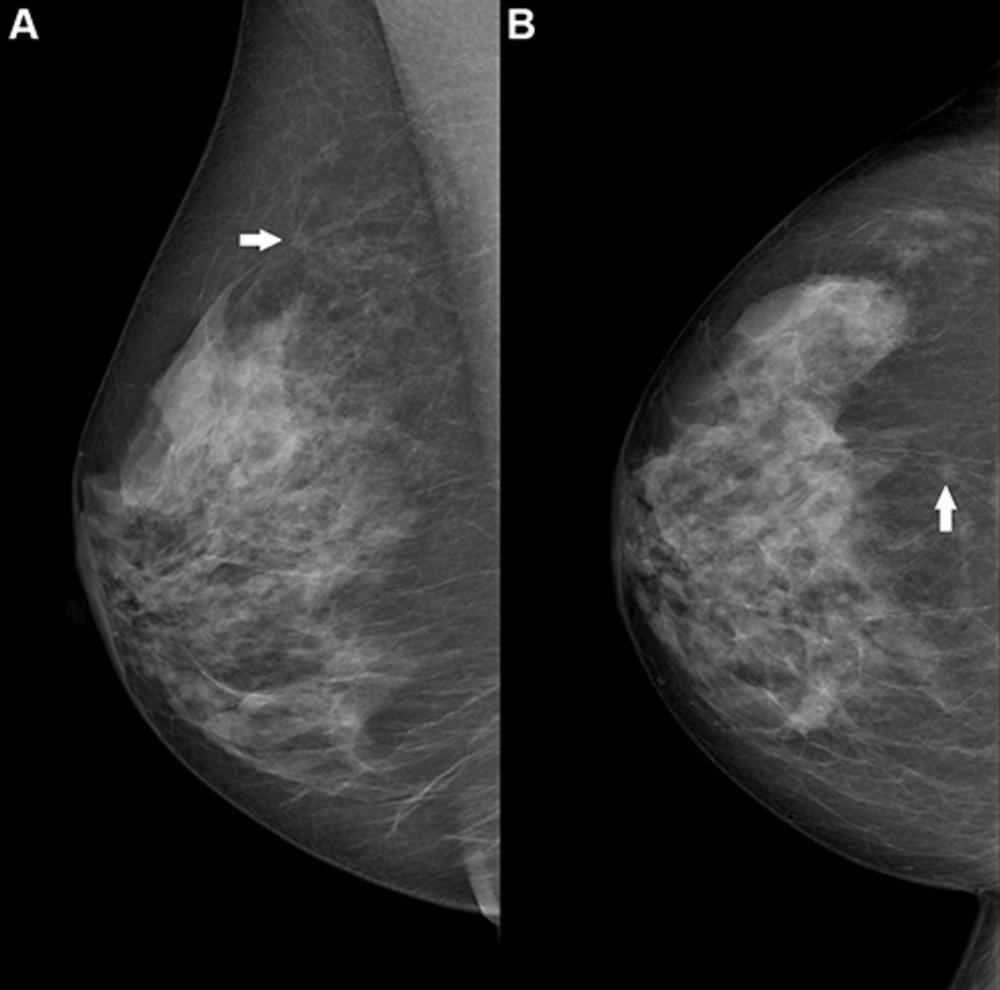

Figure 2. Right breast mammogram in a 69-year-old woman. There is a 6-mm spiculate mass in the 12 o’clock position (arrow), visible on both the (A) mediolateral oblique and (B) craniocaudal views. This case was not recalled by any of the top 10 artificial intelligence algorithms but was a biopsy-proven invasive carcinoma.